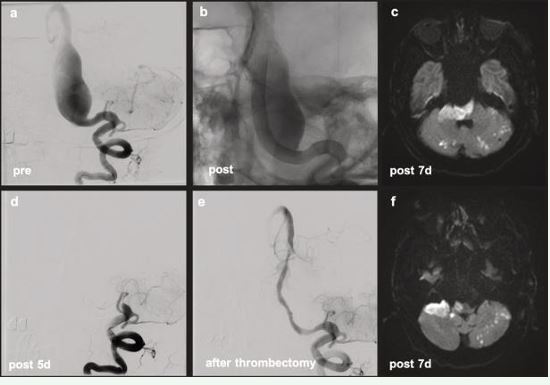

Patient 1

An 81-year-old man referred with a diagnosis of a usiform aneurysm of the basilar artery (BA) had recurrent headaches and visual disturbances. MRI showed a 2.5 cm fusiform aneurysm with significant wall enhancement and brainstem compression. He received loading doses of prasugrel, aspirin, and dabigatran. Platelet function tests measured by Multiplate and VerifyNow assays confirmed adequate inhibition. The patient underwent implantation of five overlapping flow-diverters (FD). Post-operatively, triple antithrombotic therapy was continued. One day post-discharge, the patient developed diplopia and dizziness. MRI revealed new ischemic lesions. Despite continued antiplatelet efficacy, neurological deterioration followed. CT angiography showed FD occlusion. The anticoagulant response to dabigatran was assessed using the ClotChek™ POC device. Clotting Time was 194 seconds, which was below the normal clotting time range (200–290 seconds), thus indicating insufficient dabigatran anticoagulation effect. Emergency thrombectomy restored flow, but ischemic injury progressed. A second thrombectomy was performed, but the patient developed locked-in syndrome and died four days later (Figure 1).

Figure 1 PT 1 Diagnostic: fusiform BA aneurysm (a). Post-treatment without subtraction (b): perfectly adapted FDs from distal left V4 segment to mid BA. Day 5: FD occlusion (d). Successfully recanalized (e). Day 7 MRI: progressive ischemic changes in the brainstem and cerebellum (c, f).

Non-saccular fusiform basilar artery aneurysms represent a particularly high-risk neurovascular pathology with limited therapeutic options and poor natural history [10,11]. Endovascular reconstruction using overlapping flow diverters (FDs) has emerged as a technically feasible strategy, yet carries substantial procedural risk, including thromboembolic and ischemic complications [12,13]. Antiplatelet and anticoagulant therapy is central to reducing this risk, with recent data supporting triple therapy regimens involving two antiplatelet agents and one DOAC. Despite standardized DOAC dosing, clinical outcomes remain heterogeneous. This variability could reflect a clinically relevant spectrum of anticoagulant response among patients. Real-world evidence shows that approximately 20% of patients treated with DOACs for atrial fibrillation experience breakthrough ischemic strokes, raising concern for suboptimal pharmacodynamic effect [8]. Such patients may not achieve sufficient thrombin or factor Xa inhibition despite appropriate plasma levels. Pharmacodynamic failure may be especially consequential in the neurointerventional setting, where clot formation on stent constructs or within aneurysm sacs can result in brainstem infarction or death. The cases presented here exemplify both ends of the DOAC response spectrum. ClotChek™ testing in Patient 1 demonstrated insufficient dabigatran effect, which likely contributed to the development of catastrophic FD thrombosis. This case highlights the inadequacy of relying solely on standard dosing protocols and the need for real-time, point-of-care coagulation testing. Patient 2, in contrast, exhibited a therapeutic response by ClotChek™ and maintained patency of the stent construct, with ischemia likely attributable to hemodynamic and anatomical factors rather than pharmacologic failure. These findings reinforce the concept that pharmacodynamic variability in DOAC response can have significant clinical consequences. Incorporating bedside coagulation testing into neurointerventional practice could guide therapeutic adjustments and ultimately enhance patient outcomes. Further studies are needed to validate these findings and establish standardized protocols for measuring DOAC effect in high-risk populations.